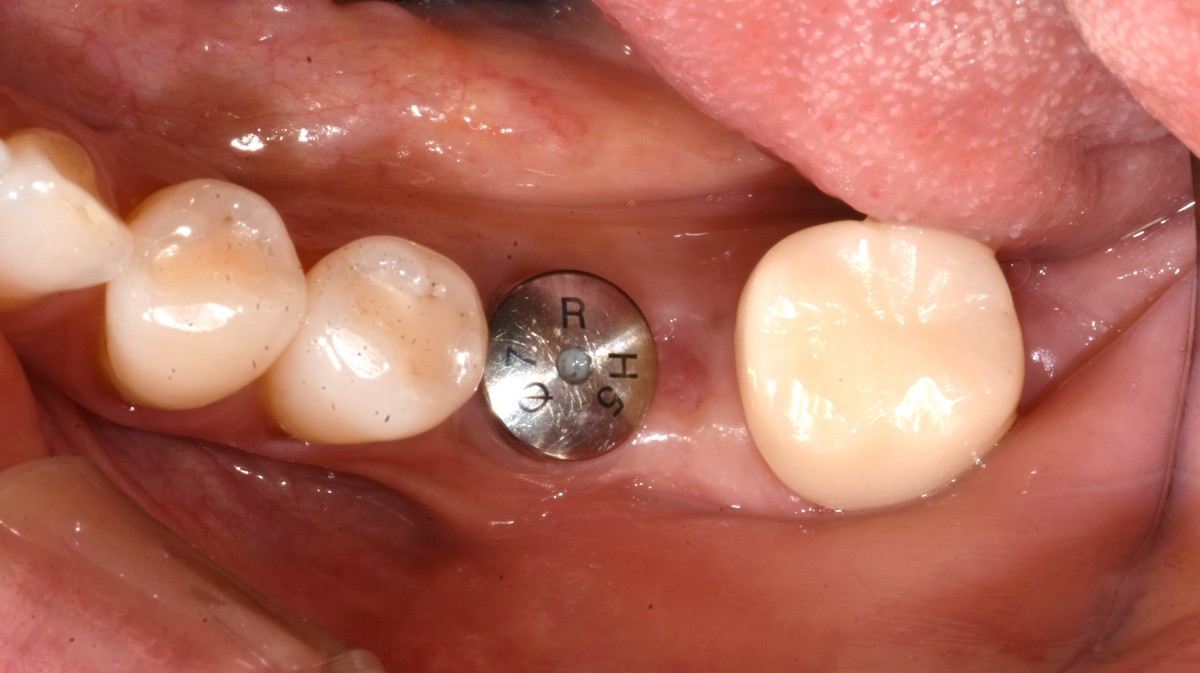

Immediate placement of an implant (Arum Dnetistry NB1, 5*8.5)

▲Arum Dentistry NB1 fixture (5*8.5mm)